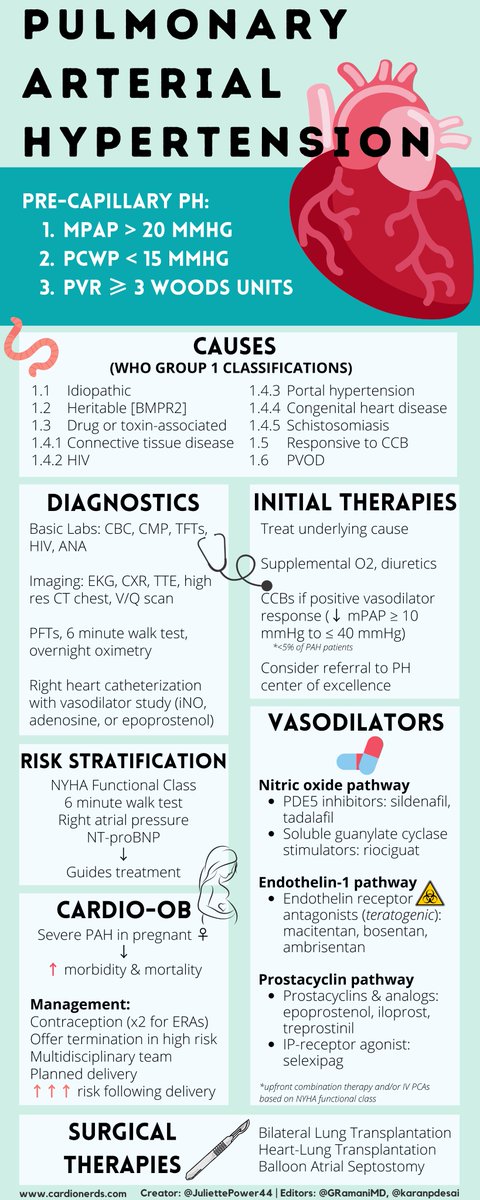

🫀Pulmonary Arterial Hypertension 🫁 In this infographic for CardioNerds Academy, we discuss diagnosis & management of PAH! Thanks to Gautam Ramani Karan Desai MD FACC Amit Goyal MD MAS